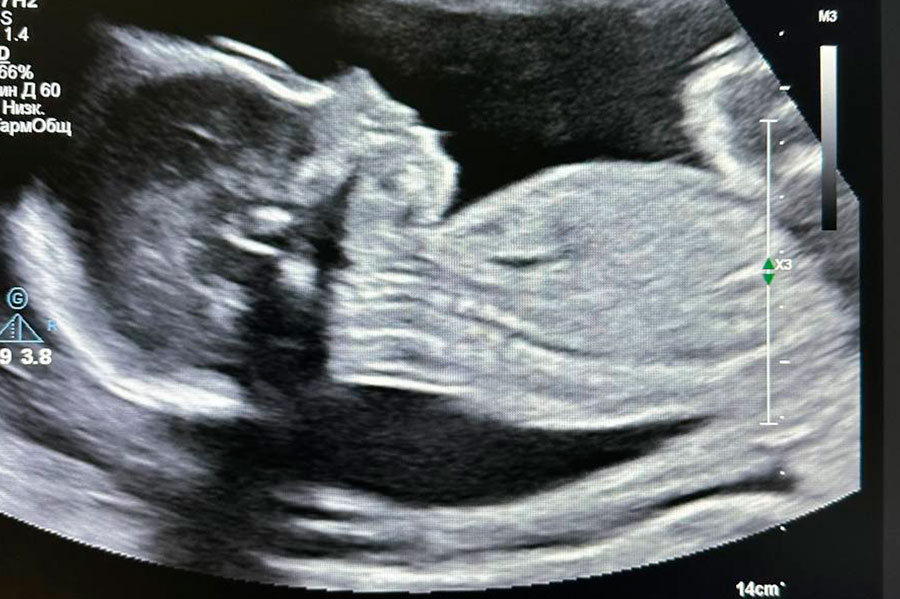

Пациентке 33 года, и в момент хирургического вмешательства женщина была на 23-й недели беременности. Несмотря на положение белоруски, операцию решили не откладывать.

Во время хирургического вмешательства женщина находилась на искусственном кровообращении. Удаление миксомы левого предсердия (доброкачественная опухоль) проходило с применением высокотехнологичного оборудования.

"Операция и послеоперационный период прошли без осложнений. Беременность удалось пролонгировать [продлить. – Tochka.by] до 38 недель", – рассказали в медучреждении.

Так, 2 октября родился доношенный мальчик весом 3230 г и ростом 52 см. Роды были искусственными: в результате планового кесарева сечения. По шкале Апгар (дыхание, быстрота реакции, сердечный ритм, тонус мышц и так далее) у ребенка удовлетворительные показатели. Он здоров.